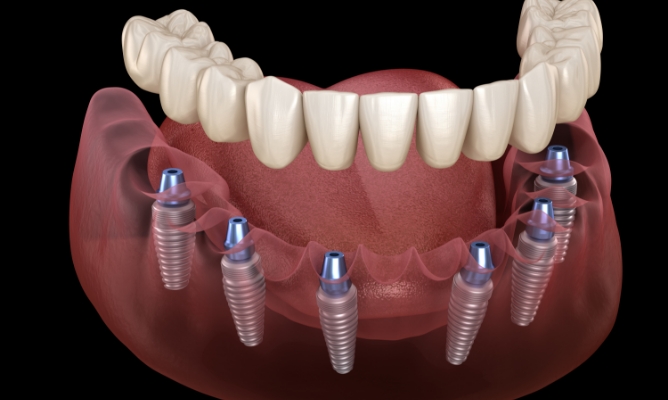

전악 임플란트

다수의 치아를 상실했을 경우 전체 식립을 통해

치아의 전반 회복이 가능한 임플란트